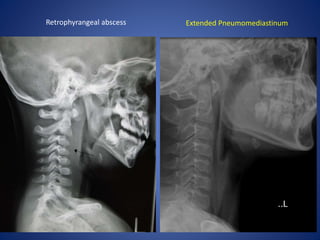

Extended Pneumomediastinum

Retrophyrangeal abscess Extended Pneumomediastinum